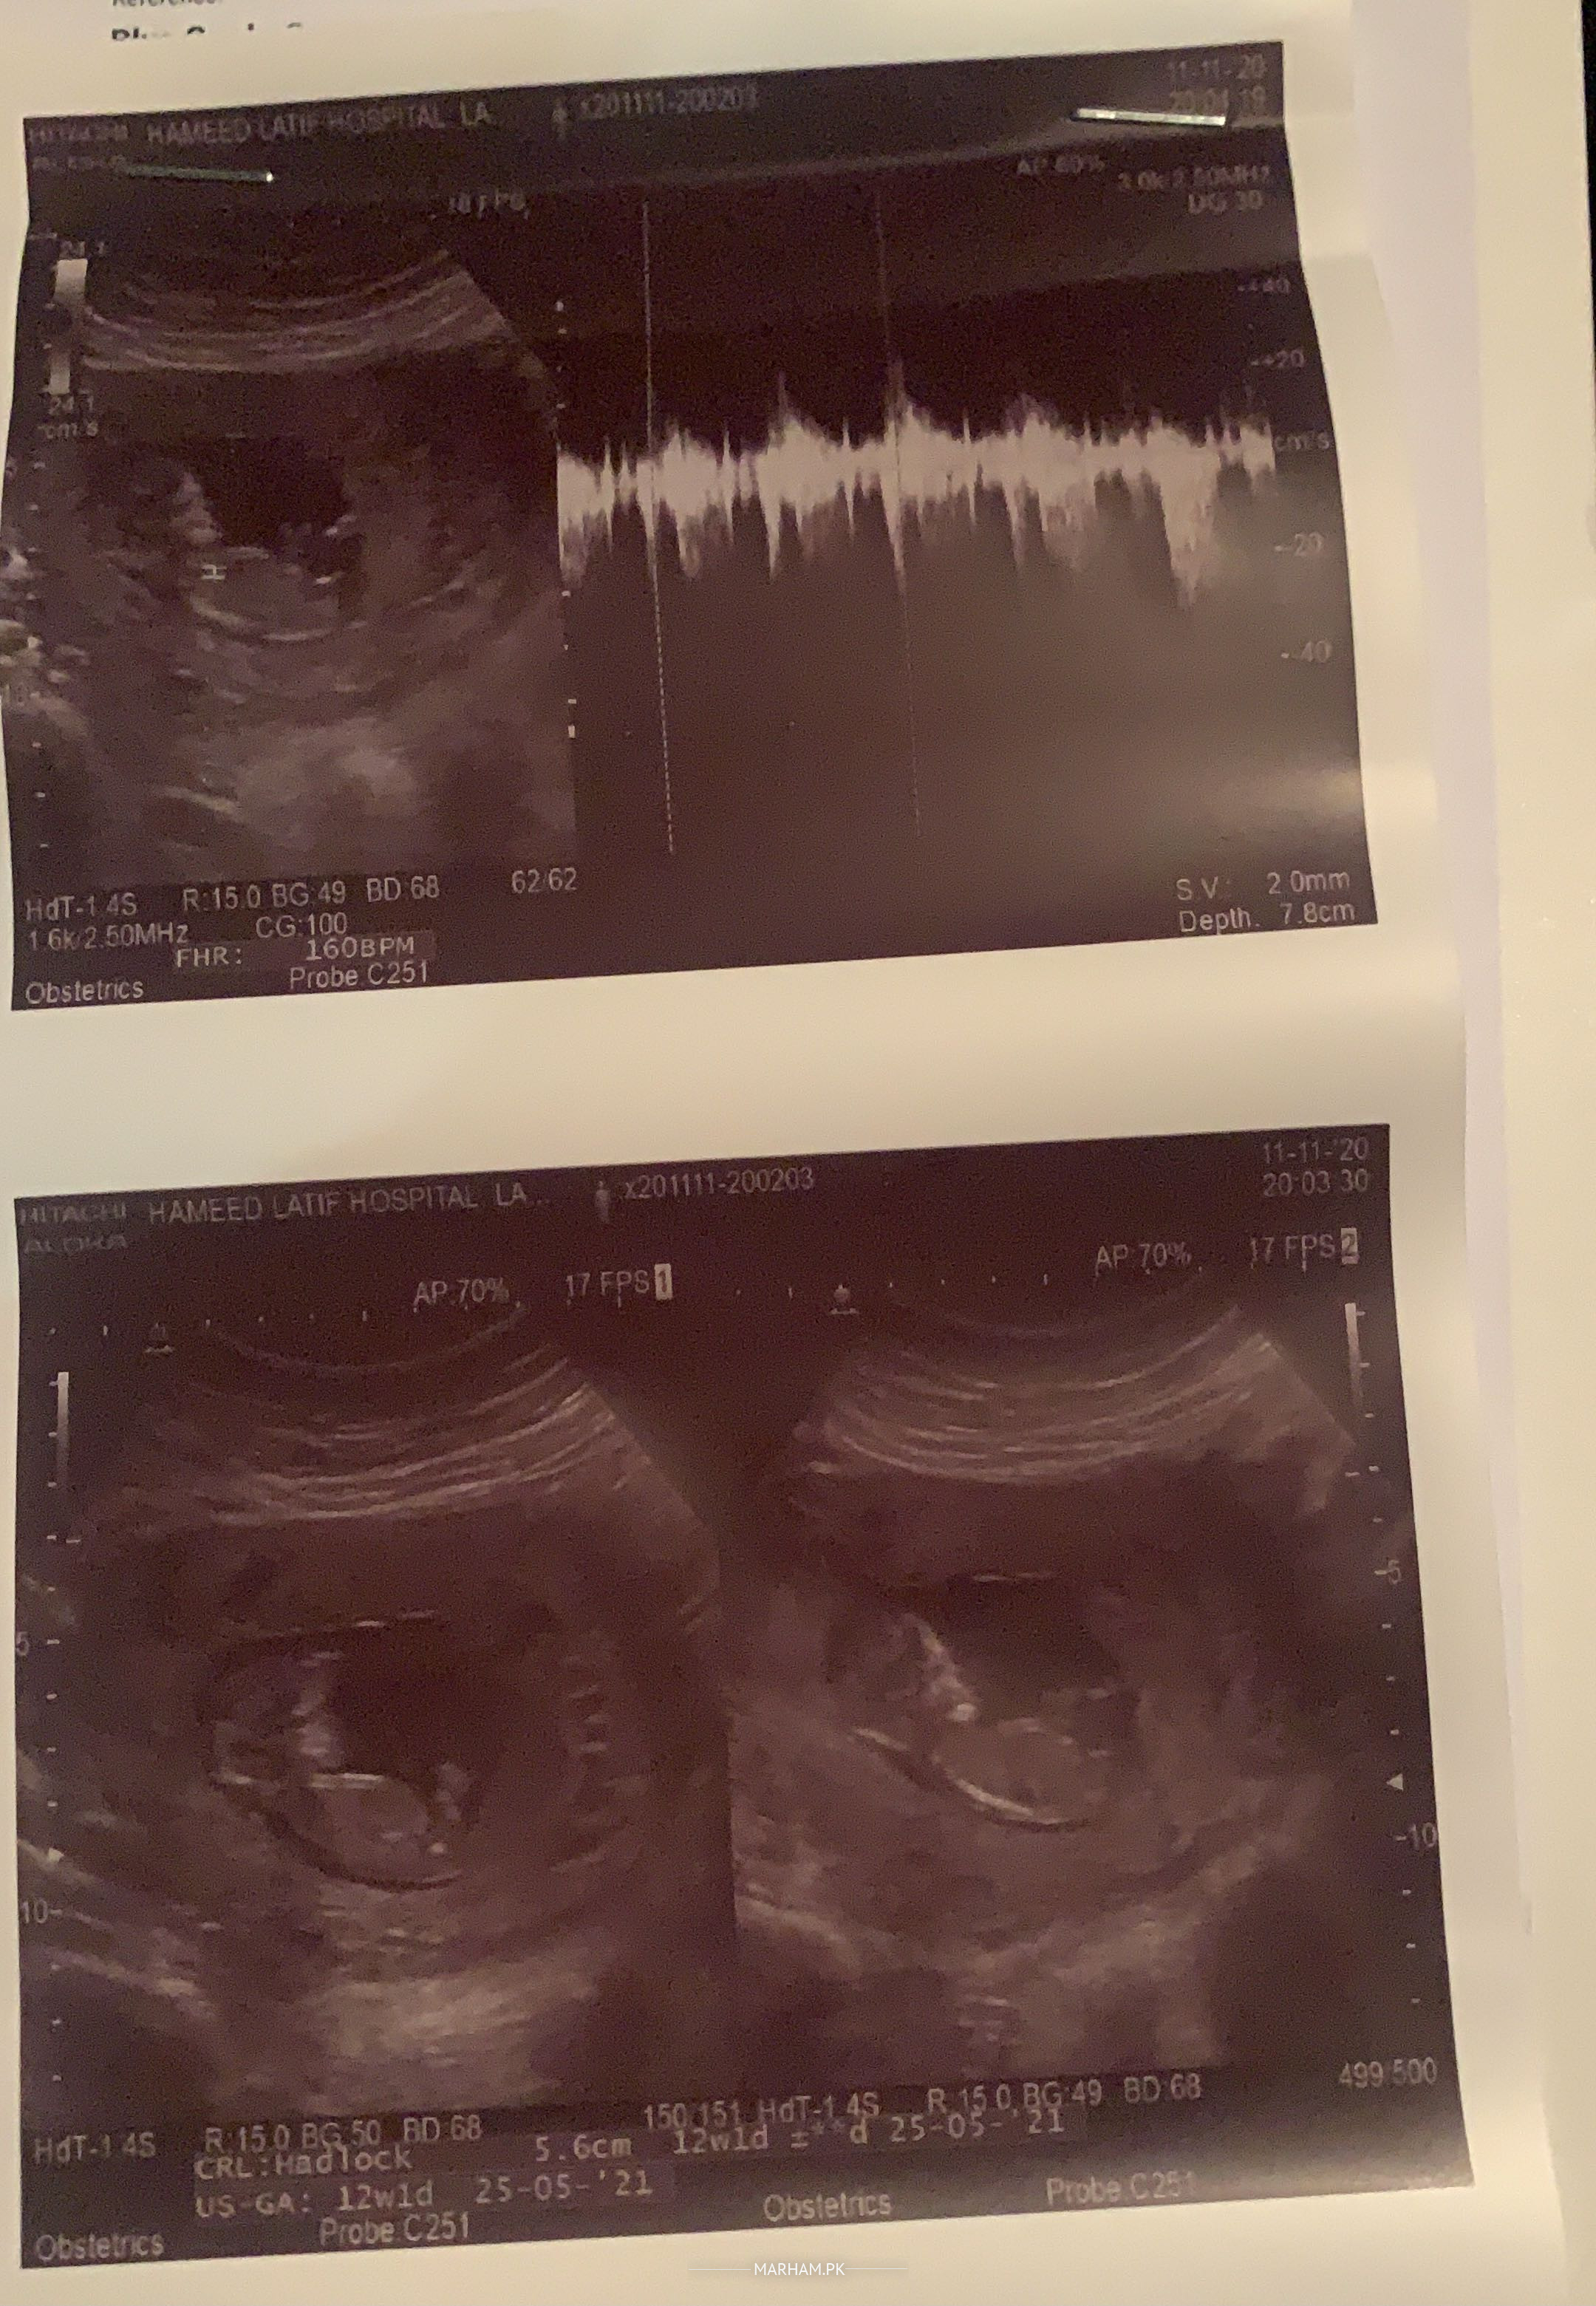

Salam I have a miscarriage history of twins. Is pregnancy mei doctor ne shuru se medicines ziyada di thin with 4 ivf injections duphaston loprin aur progesterone vaginally. Alhamdulillah sab kuch theek hai i am 12 weeks pregnant. Mei ne extreme nausea ki wajha se 3 nonths se kuch khas ni khaya. Roti b ni khai na meat. Only apple and bananas and french fries. Masla yeh hai k mei jb b cooking kernay k liye ya nahany k kiye khari rehti hun tau mera dum ghutnay lag jata hai. Senay mei dard hoti hai. Sath saans asa lagta hai bnd ho jae ga. Usi time mujhay clear discharge b ziyada anay lag jata hai. 2 min se ziyada phr khara hi hua jata. Iski kiya wajha ho sakti hai. Asa mere sath last pregnancy mei b hota tha. Phr missed miscarriage hua tha. Kiya mujhay cooking stop ker deni chahiye? Is sab se wajha se mere baby pe tau effect ni hota hoga? Ya yeh koi aur masla hai? Tests sab clear hain.

This ultrasound is normal, cooking should not affect your pregnancy.